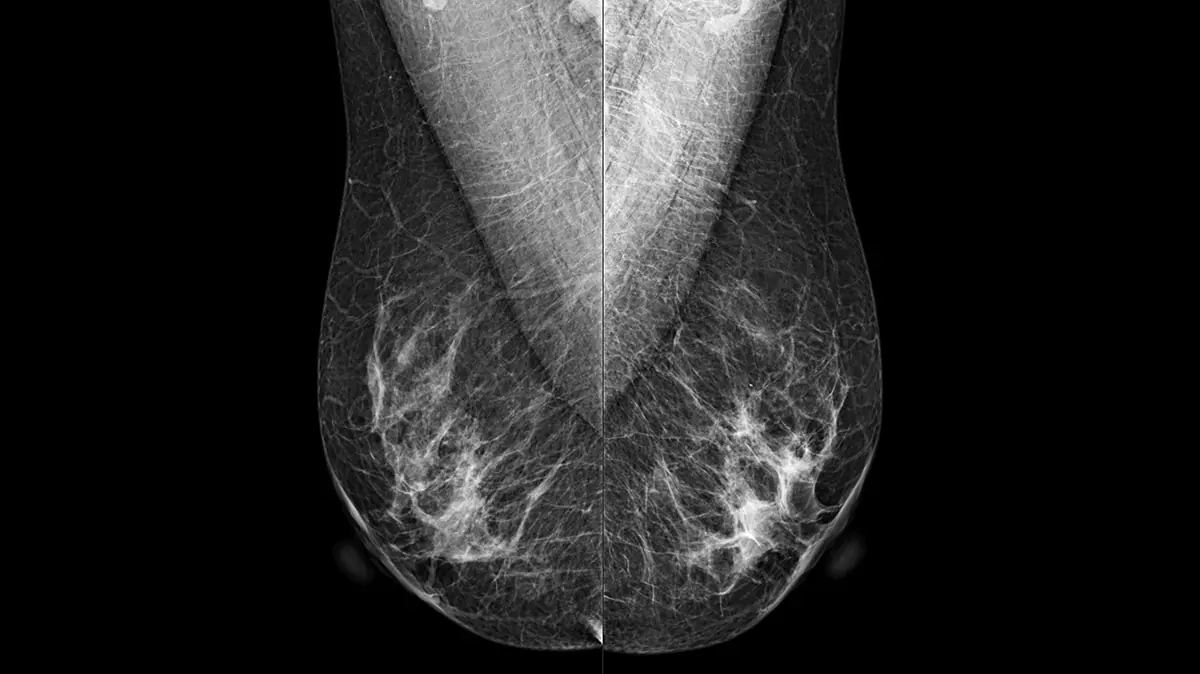

- Evaluación integral de la densidad mamaria: la densidad del tejido mamario es un factor que puede ocultar lesiones en la imagen. Cuanto más denso sea el tejido, mayor es la dificultad para detectar anomalías. Una imagen bien optimizada garantiza la correcta diferenciación entre tejido fibroglandular y adiposo, permitiendo valorar el nivel de densidad y establecer protocolos de seguimiento más ajustados al riesgo individual de cada paciente.

AIDIA LUXE permite realizar estudios en tomosíntesis, capturando múltiples imágenes desde distintos ángulos, lo que mejora la visualización de lesiones ocultas detrás de tejido superpuesto. Además, incluye generación de imagen sintética 2D derivada de los cortes 3D para que el diagnóstico siga siendo comparable con mamografías tradicionales, reduciendo la necesidad de exposiciones adicionales.

Gracias a su capacidad de capturar imágenes en ángulos estrechos de 15° y medios de 25°, AIDIA LUXE ofrece una visualización clara y definida de microcalcificaciones y estructuras finas. Esta versatilidad permite transiciones fluidas entre distintos modos de visualización (2D, 2D sintético, Slab y Plano), brindando al radiólogo herramientas completas para un análisis más detallado y confiable.